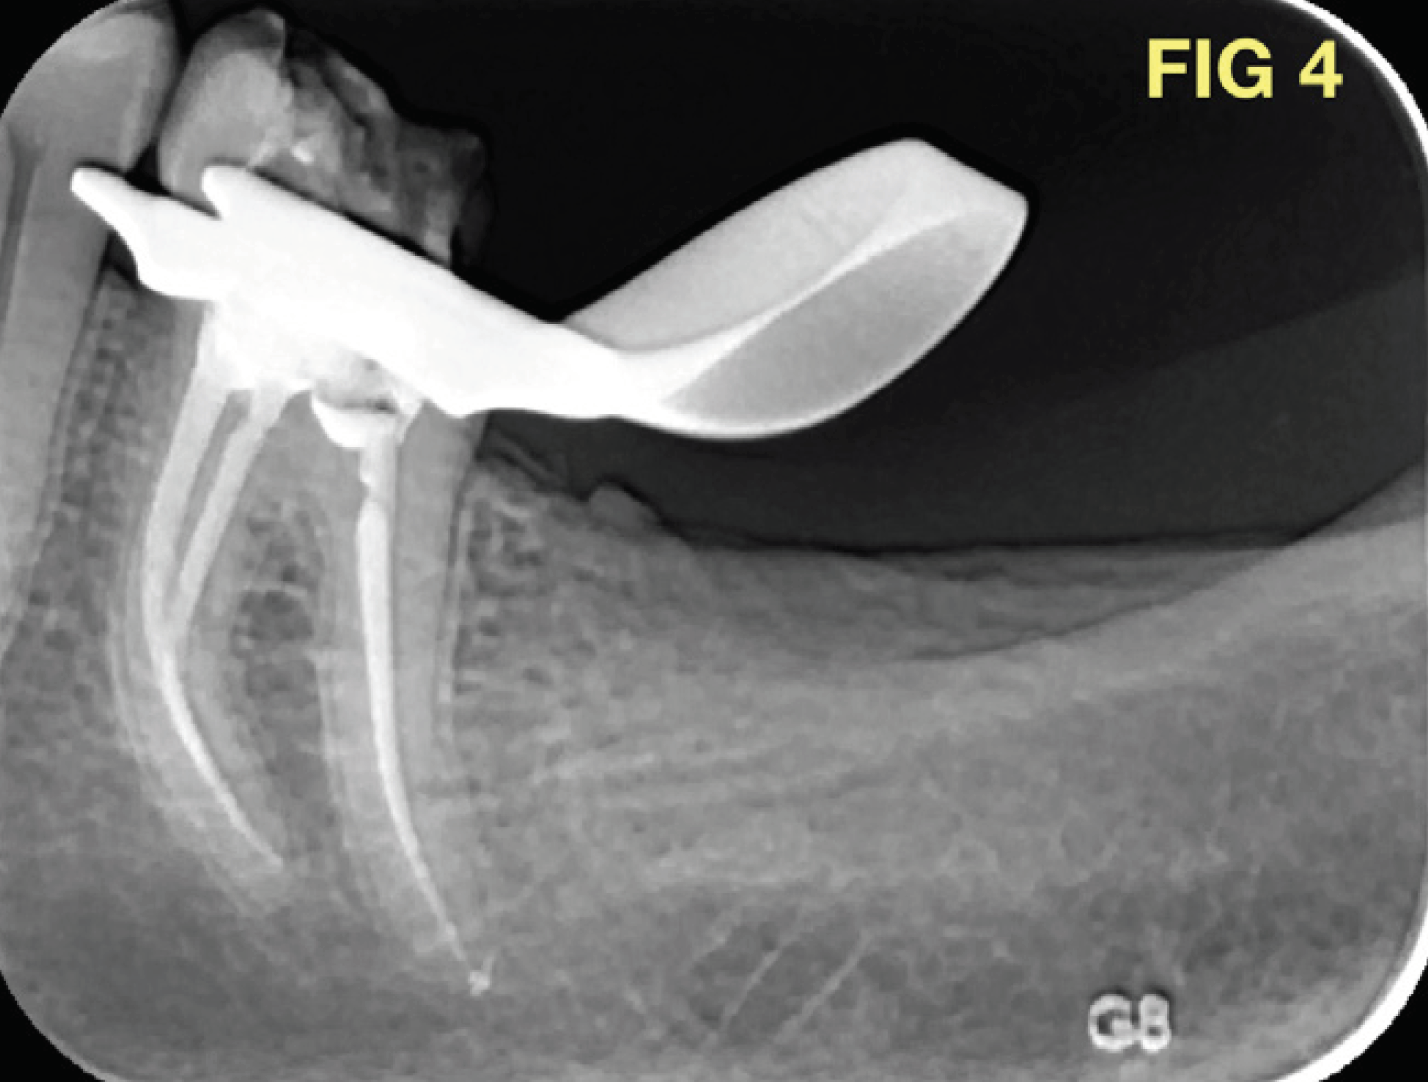

Die Abbildungen 3 und 4 zeigen das Ergebnis der endodontischen Behandlung. Die Kanalgeometrie konnte exakt eingehalten werden. Die korrekte Formgebung (Kanaldurchmesser können in 3D-Bildern besser eingeschätzt werden) wurde schnell und einfach während einer 45-minütigen Wurzelkanalbehandlung in einer Sitzung vorgenommen; ohne iatrogene Fehler, ohne Verformung oder Bruch der Instrumente.

Abschließend wurden die Kanäle mit einer Kalthydrauliktechnik unter Verwendung von Bioceramic Sealer (BC Sealer, BUSA, USA), ein Material, das eine einfache und schnelle Lösung bietet, obturiert.